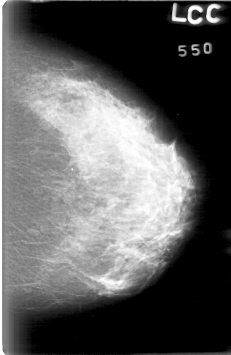

D_4022_1.LEFT_CC

LEFT_CC LINES 5311 PIXELS_PER_LINE 3451 BITS_PER_PIXEL 12 RESOLUTION 43.5 NON_OVERLAY